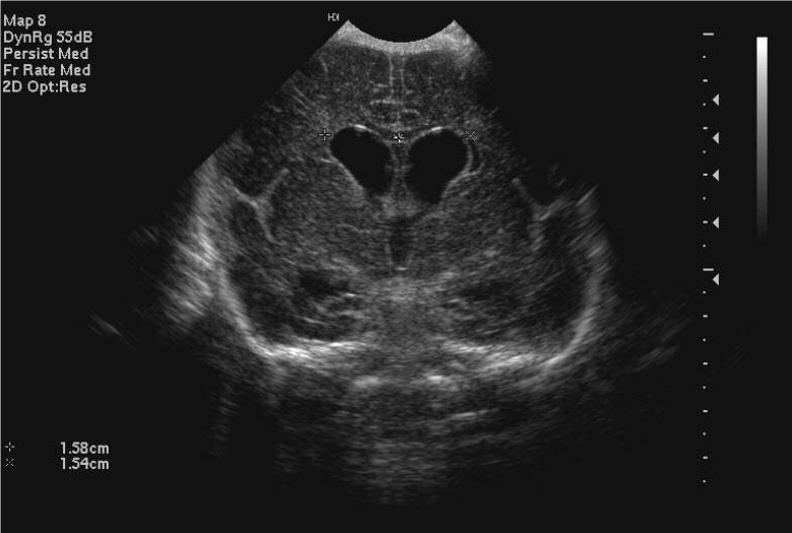

• When there is ventricular dilatation on scan, the ventricular index is measured to given an objective comparison between scans

• The ventricular index is the distance from the midline to the most lateral part of the lateral ventricle on a coronal scan taken at the level of the foramina of Munro

• The chart below gives the 3rd, 50th and 97th centiles for ventricular index by gestation